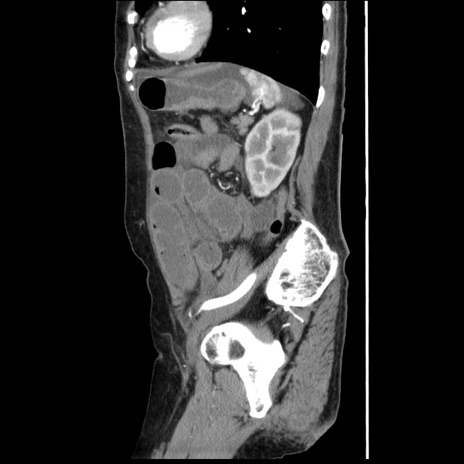

横断像

【症例】80歳代女性

【主訴】腹痛

【現病歴】8時間前から腹痛あり来院。

【既往歴】糖尿病、脂質異常症、子宮体癌にて子宮全摘術

【身体所見】意識清明・会話良好だが腹痛で苦悶様、全腹部にわたって反跳痛と圧痛あり

【データ】WBC 13600、CRP 0.14、LDH 224、CK 90